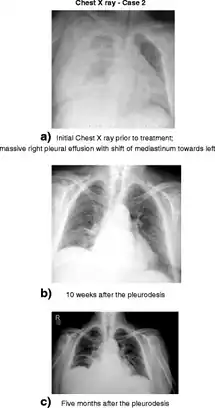

In cases where TIPS is contraindicated, another treatment option is to insert an indwelling pleural catheter (IPC).[10] Pleural treatments generally have a high complication rate;[9] in a case study, those receiving IPC had greater complication rates despite undergoing significantly less procedures.[6] As a last resort, pleurodesis can be used for people without ascites; by irritating the pleura together, it can repair any defects in the diaphragm. However, it requires multiple procedures and general anesthesia. Additionally, the amount of pleural fluid produced can overcome pleurodesis, causing it to fail.[9] Complications may include empyema, sepsis, and septic shock. Chest tubes and intercostal chest drains are contraindicated, as they can cause loss of protein, infection, pneumothorax, hemothorax, and electrolyte imbalances. Additionally, removing them may pose a challenge, as the fluid returns extremely quickly afterward.[5] Palliative care can also help with symptoms; for people resistant to disease-related treatment, no preferred methods exist to manage symptoms for this condition.[6]